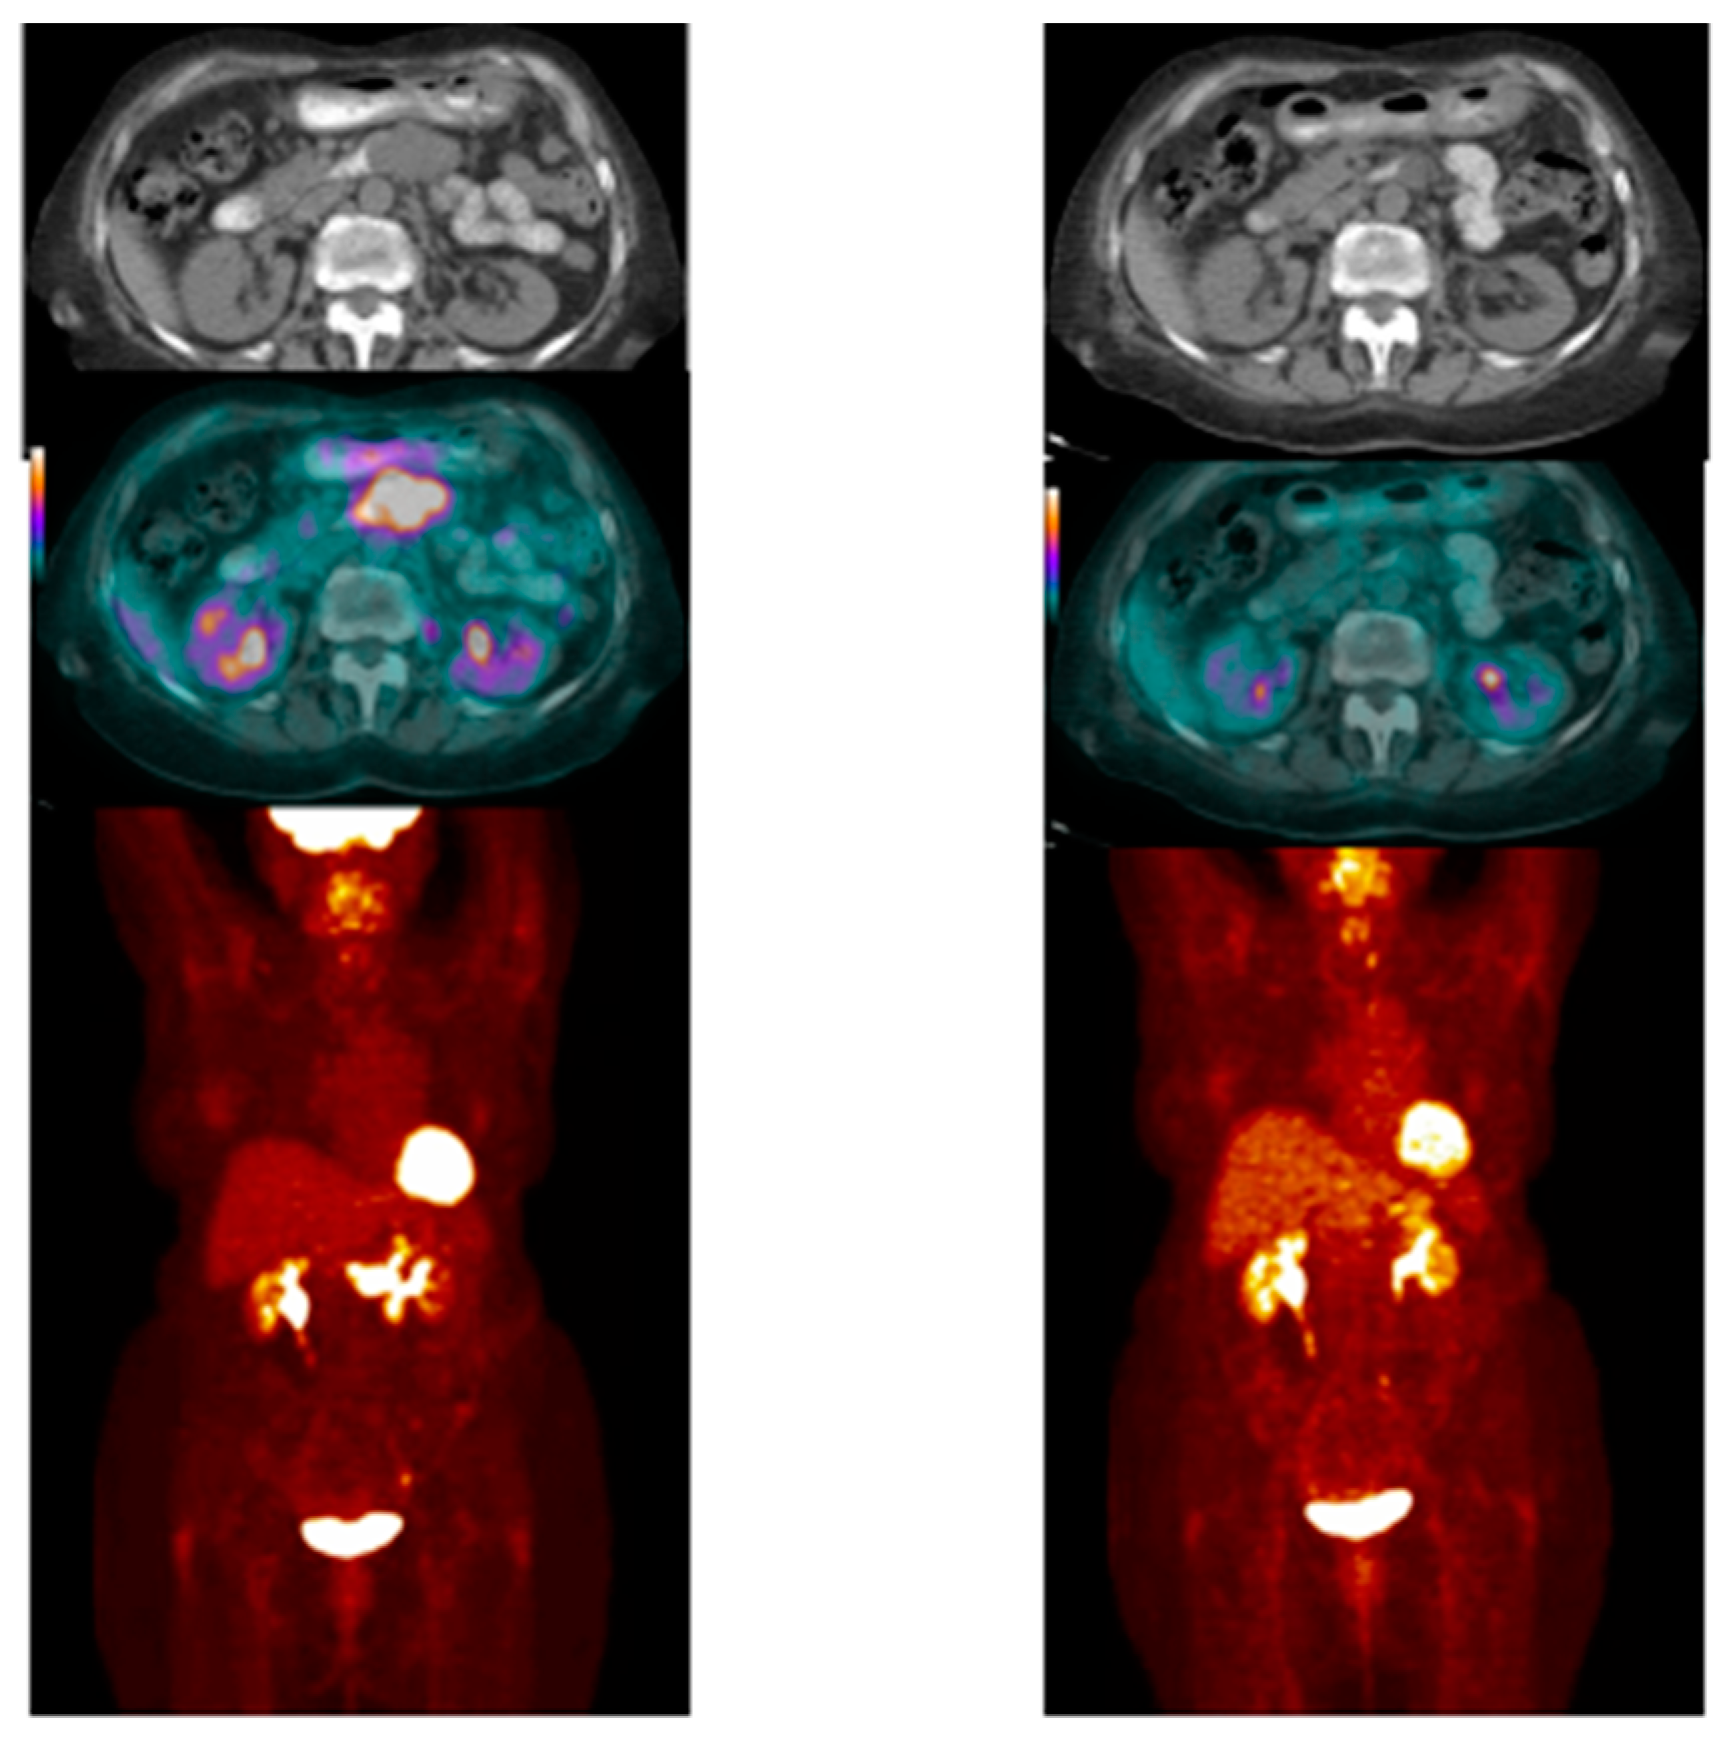

- Case # 3:

- This is a 46 year old female with recurrent GIST. She had multiple prior therapies including imatinib, sunitinib, regorafenib, nilotinib, and pazopanib. After 2 weeks of new therapy with a novel TKI targeting c-KIT, she had a complete metabolic response, but only a partial anatomic response. This showcases early response can be seen as early as 2 weeks in GIST another sarcoma like Ewing’s sarcoma where in early responses as early as 9 days have been shown to predict survival [38] (Figure 4).